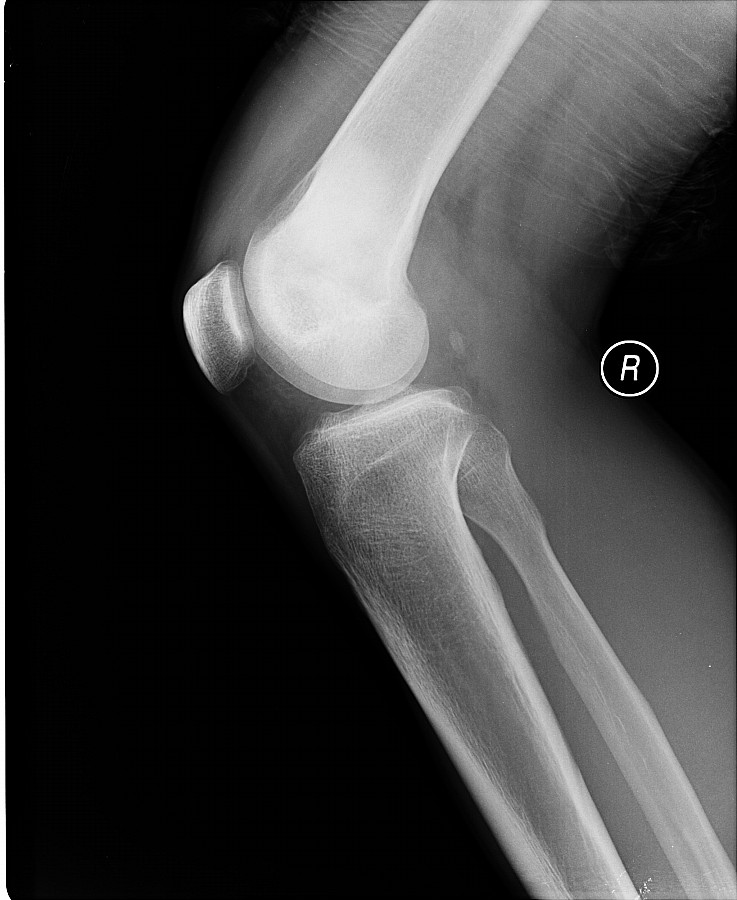

以下是引用黑白光影在2009-3-13 13:00:00的发言:[br]考虑右股骨远端内侧缘絮样骨质密度影,髁上可见骨膜反应,相应侧软组织肿胀,考虑成骨肉瘤可能。

以下是引用guo430726在2009-3-13 13:50:00的发言:[br]考虑右股骨远端内侧缘絮样骨质密度影,髁上可见骨膜反应,相应侧软组织肿胀,考虑成骨肉瘤可能。[br]支持!